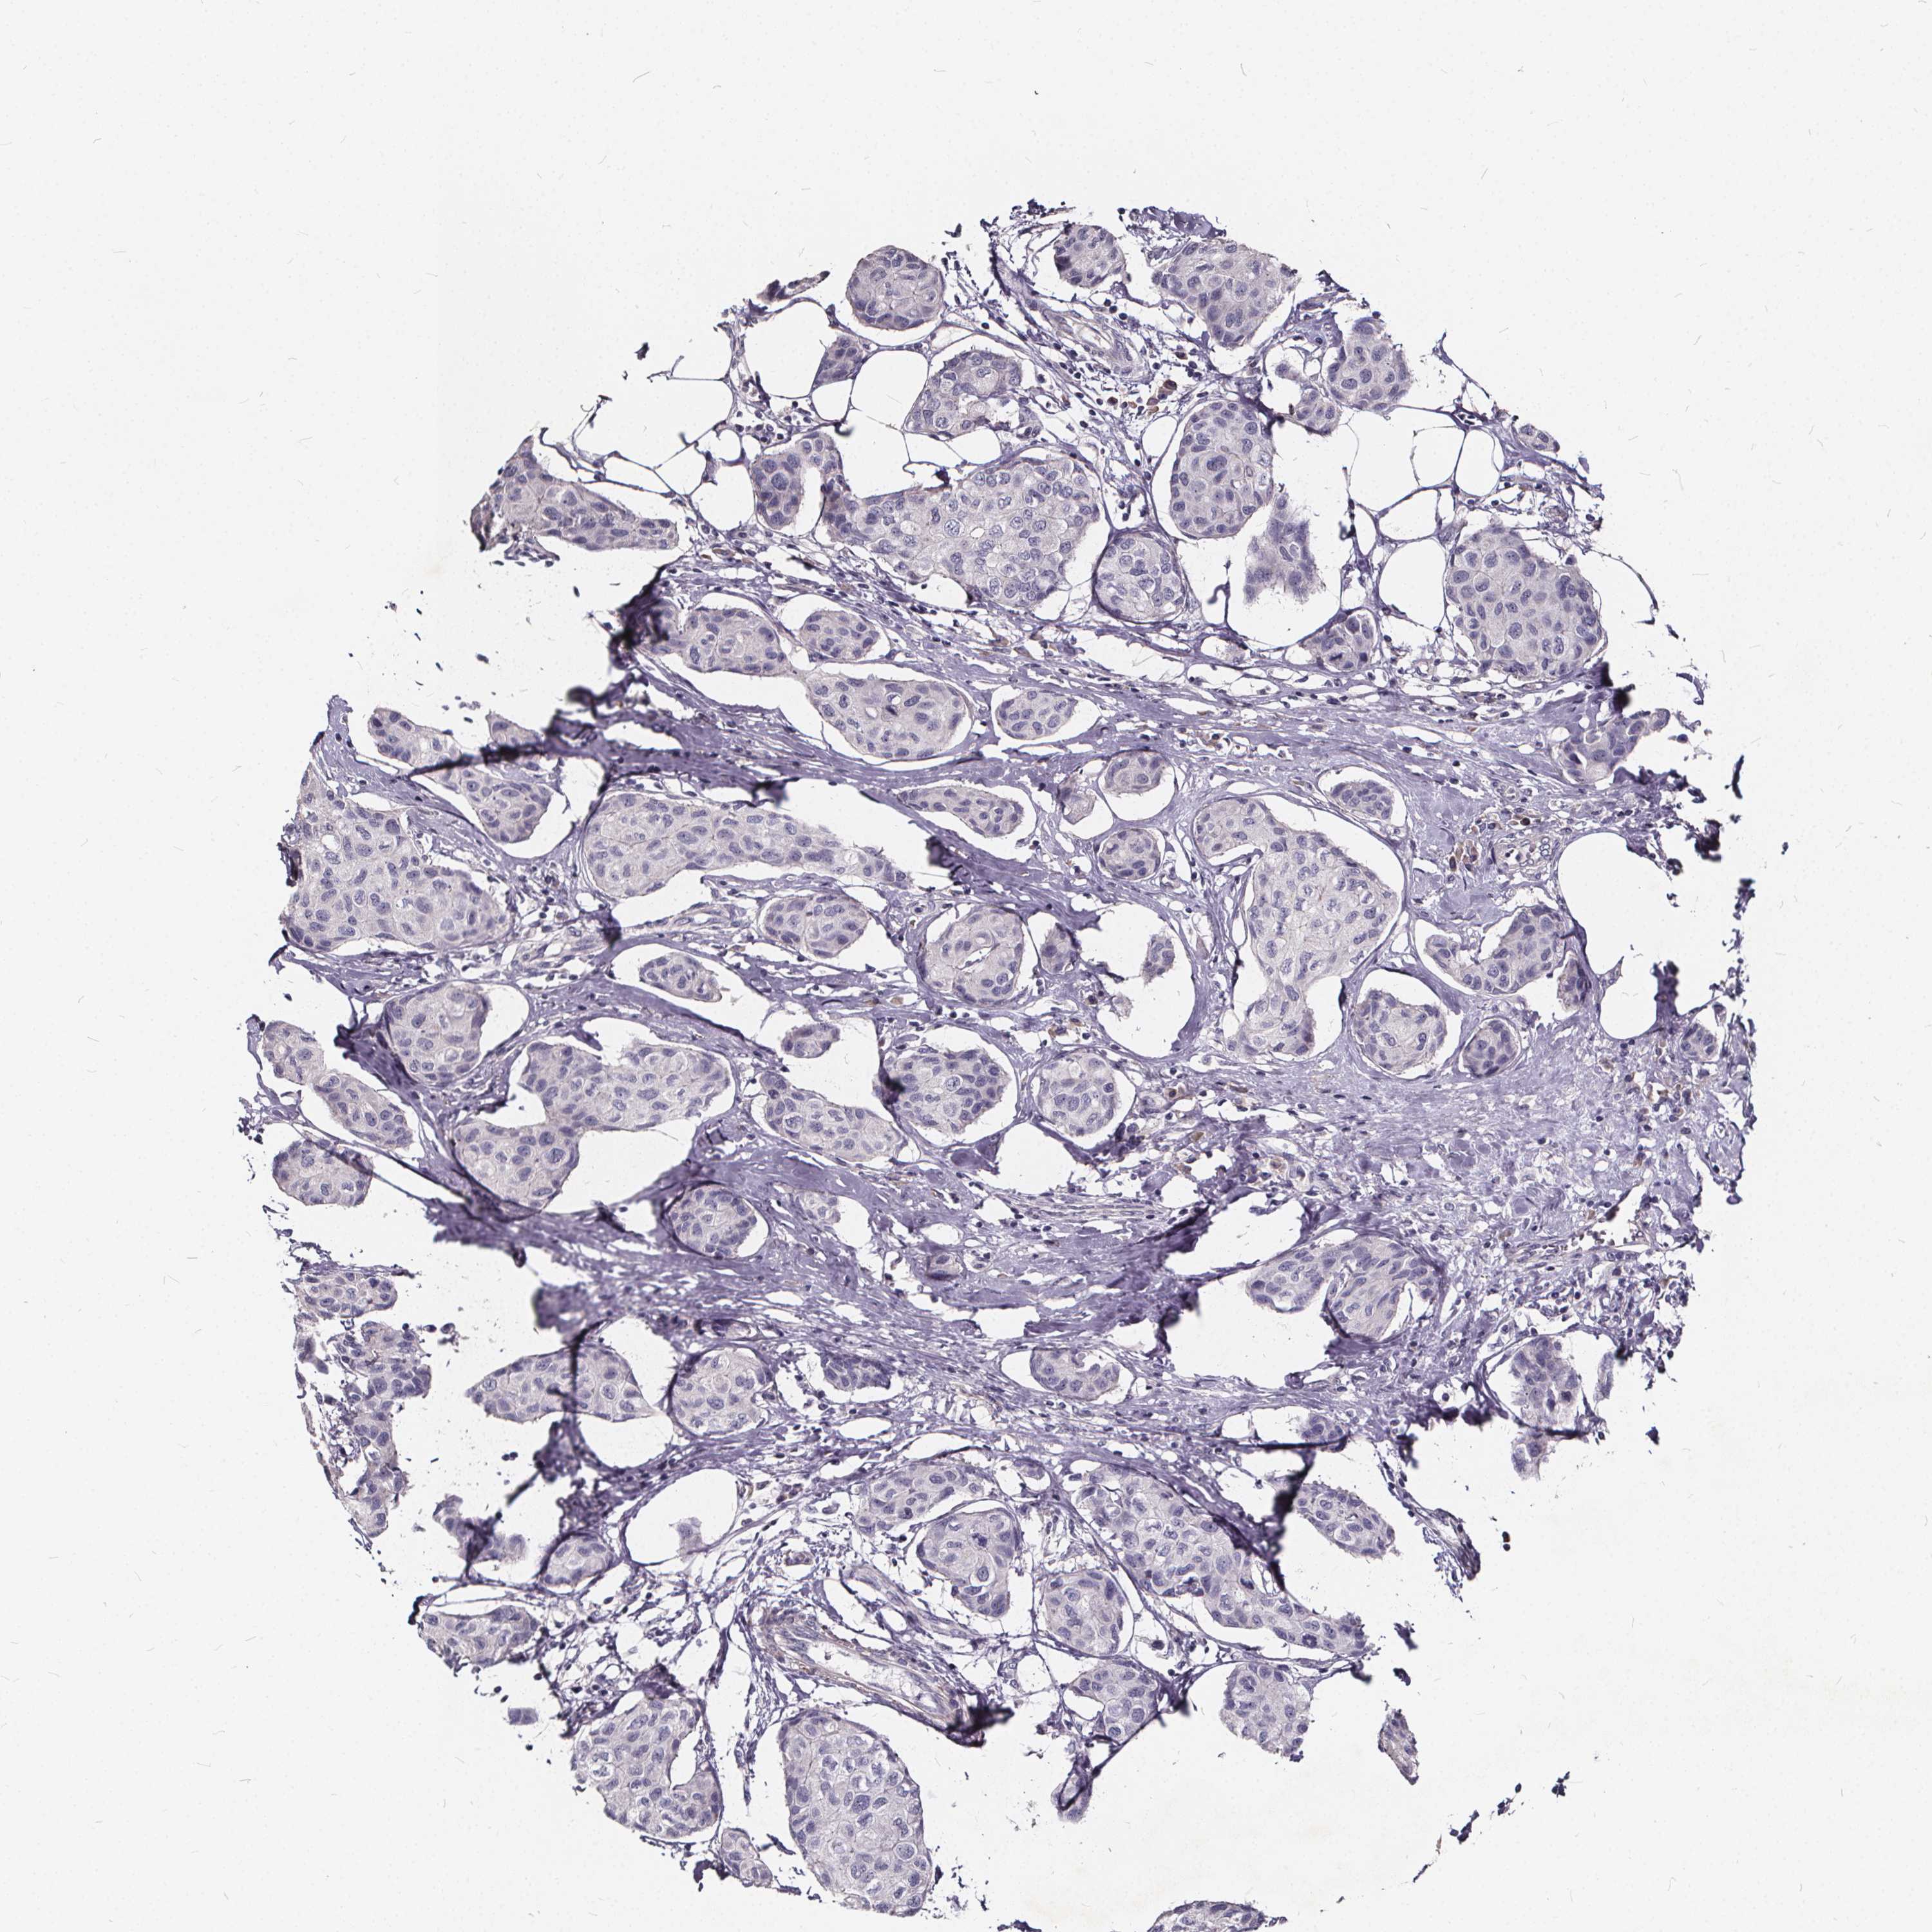

CANCER BREAST CANCER Show tissue menu

BRCA TCGA BRCA VALIDATION PROTEIN EXPRESSION